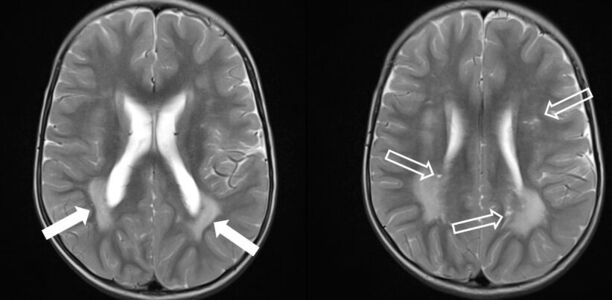

Ein Junge wird für eine zweite Meinung zu einer unklaren Leukenzephalopathie vorgestellt. Bei der Untersuchung fallen eine Makrozephalie, Pigmentflecken auf der Glans penis und narbige Veränderungen am rechten Fußrücken nach Entfernung einer "Warze" auf. Wie lautet Ihre Verdachtsdiagnose?

Ein 2-jähriger Junge mit Makrozephalie und Leukenzephalopathie